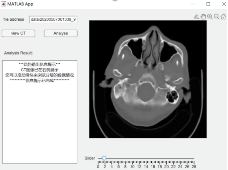

实践课的成果:实现了对颅骨、大脑软组织以及血肿部分的分割,并建立了三维可视化模型,实现了对脑出血的量、形态、结构进行测量和判断;开发了集成脑出血量计算结果、三维可视化等内容在内的用户图形界面。

部分成果展示

图1.脑部分割结果的三维可视化

图2.GUI显示不同断层的CT扫描结果

图3. GUI显示脑部分割结果三维可视化及相关信息

张旨晗:在本次实践中,我学到了CT图像的一些处理算法(比如生长算法等),以及MATLAB中一些功能的实现、血肿特征提取等知识。我自己的博士课题是有关SPECT/CT系统上的SPECT系统设计和算法研究,本次暑期实践让我对CT有关知识有了更加深刻的理解和认识。